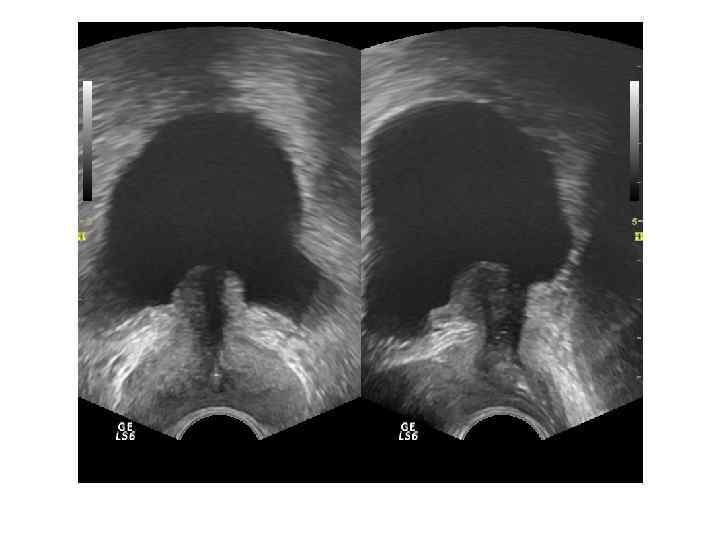

ДГПЖ Доброкачественная гиперплазия простаты – заболевание , характеризующееся гиперплазией железистых и стромальных элементов ткани предстательной железы. Основными источниками ДГПЖ являются переходные зоны и зона периуретральных желез.

Если происходит преимущественный рост переходных зон, образуются латеральные доли. Зональная анатомия предстательной железы при ДГПЖ. При ДГПЖ увеличивается объем переходной зоны (Tz), размеры центральной зоны (Cz) и периферической зоны (Pz) уменьшаются. Vm — семенной бугорок, А — фибромускулярная строма.

При росте периуретральных желез (ограниченных препростатическим сфинктером) образуется средняя доля.

При ДГПЖ меняются форма, размеры, структура и соотношение частей железы. Форма становится шаровидной или неправильной с выбуханием контура в просвет мочевого пузыря. При росте переходных зон происходит значительное увеличение размеров, но это не приводит к выраженной обструкции уретры. При росте периуретральных желез простата увеличена незначительно, но происходит сдавление уретры выбухающей средней долей. Структура гиперплазированных узлов неоднородная, часто с дегенеративными изменениями ( кисты, участки склероза, кальцификаты).